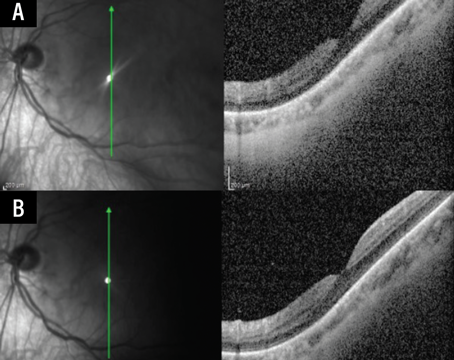

Retinal microvascular metrics: The emerging role of swept-source OCT angiography